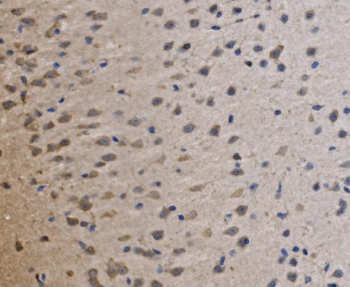

50 μl, 100 μl - MARK3 Recombinant Rabbit Monoclonal Antibody [orb704310]Featured

ICC, IF, IHC-Fr, IHC-P

Human, Mouse

Rat

Rabbit

Recombinant

Unconjugated

50 μl, 100 μl - Featured